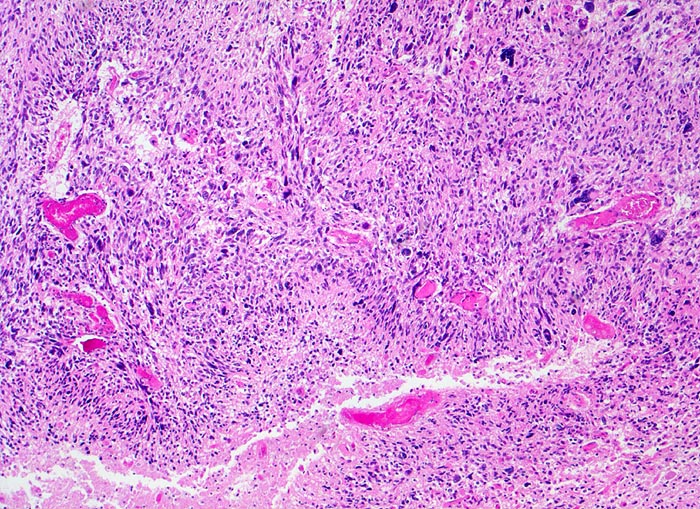

Ein Glioblastom liegt vor, wenn mindestens 3 der folgenden 4 histologischen Kriterien erfüllt sind: Kernatypien (Hyperchromasie und/oder Form- und Grössenvariabilität), Mitosen, Endothelproliferation (Gefässlumina von mehr als einer Lage Endothelzellen umgeben) und flächenhafte oder girlandenartig angeordnete Nekrosen. Ein Teil der Glioblastome entwickelt sich sekundär aus diffusen Astrozytomen Grad II. Bei den übrigen handelt es sich um sogenannt "de novo" entstandene Glioblastome.

Morphologische Merkmale:

• Zellreicher Tumor mit sehr unscharfer Begrenzung zum normalen Hirnparenchym (rechts unten).

• Typische streifenförmige Nekrosen mit randständiger Palisadierung der Tumorzellen.

• Im Zentrum der Nekrose thrombosierte Gefässe umgeben von einem Saum vitaler Tumorzellen.

• Pathologische glomerulumartige zellreiche Gefässknäuel.

• Ausgeprägte Zellpolymorphie und Atypie.

• Mitosen.